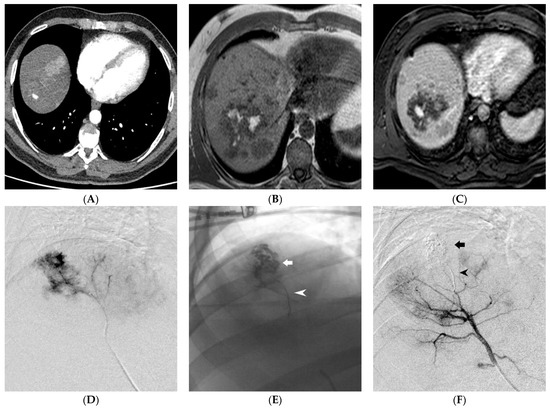

| Site of bleeding - Pelvic - Upper GI - Lower GI - Abdomen - Thorax - Neck - Limbs | 15 (28.4%) 4 (7.5%) 2 (3.8%) 18 (34%) 8 (15%) 2 (3.8%) 4 (7.5%) |

| Cause of bleeding - Trauma - Spontaneous - Others (tumors, diverticula, ulcers, etc.) | 31 (58.5%) 5 (9.4%) 16 (32.1%) |